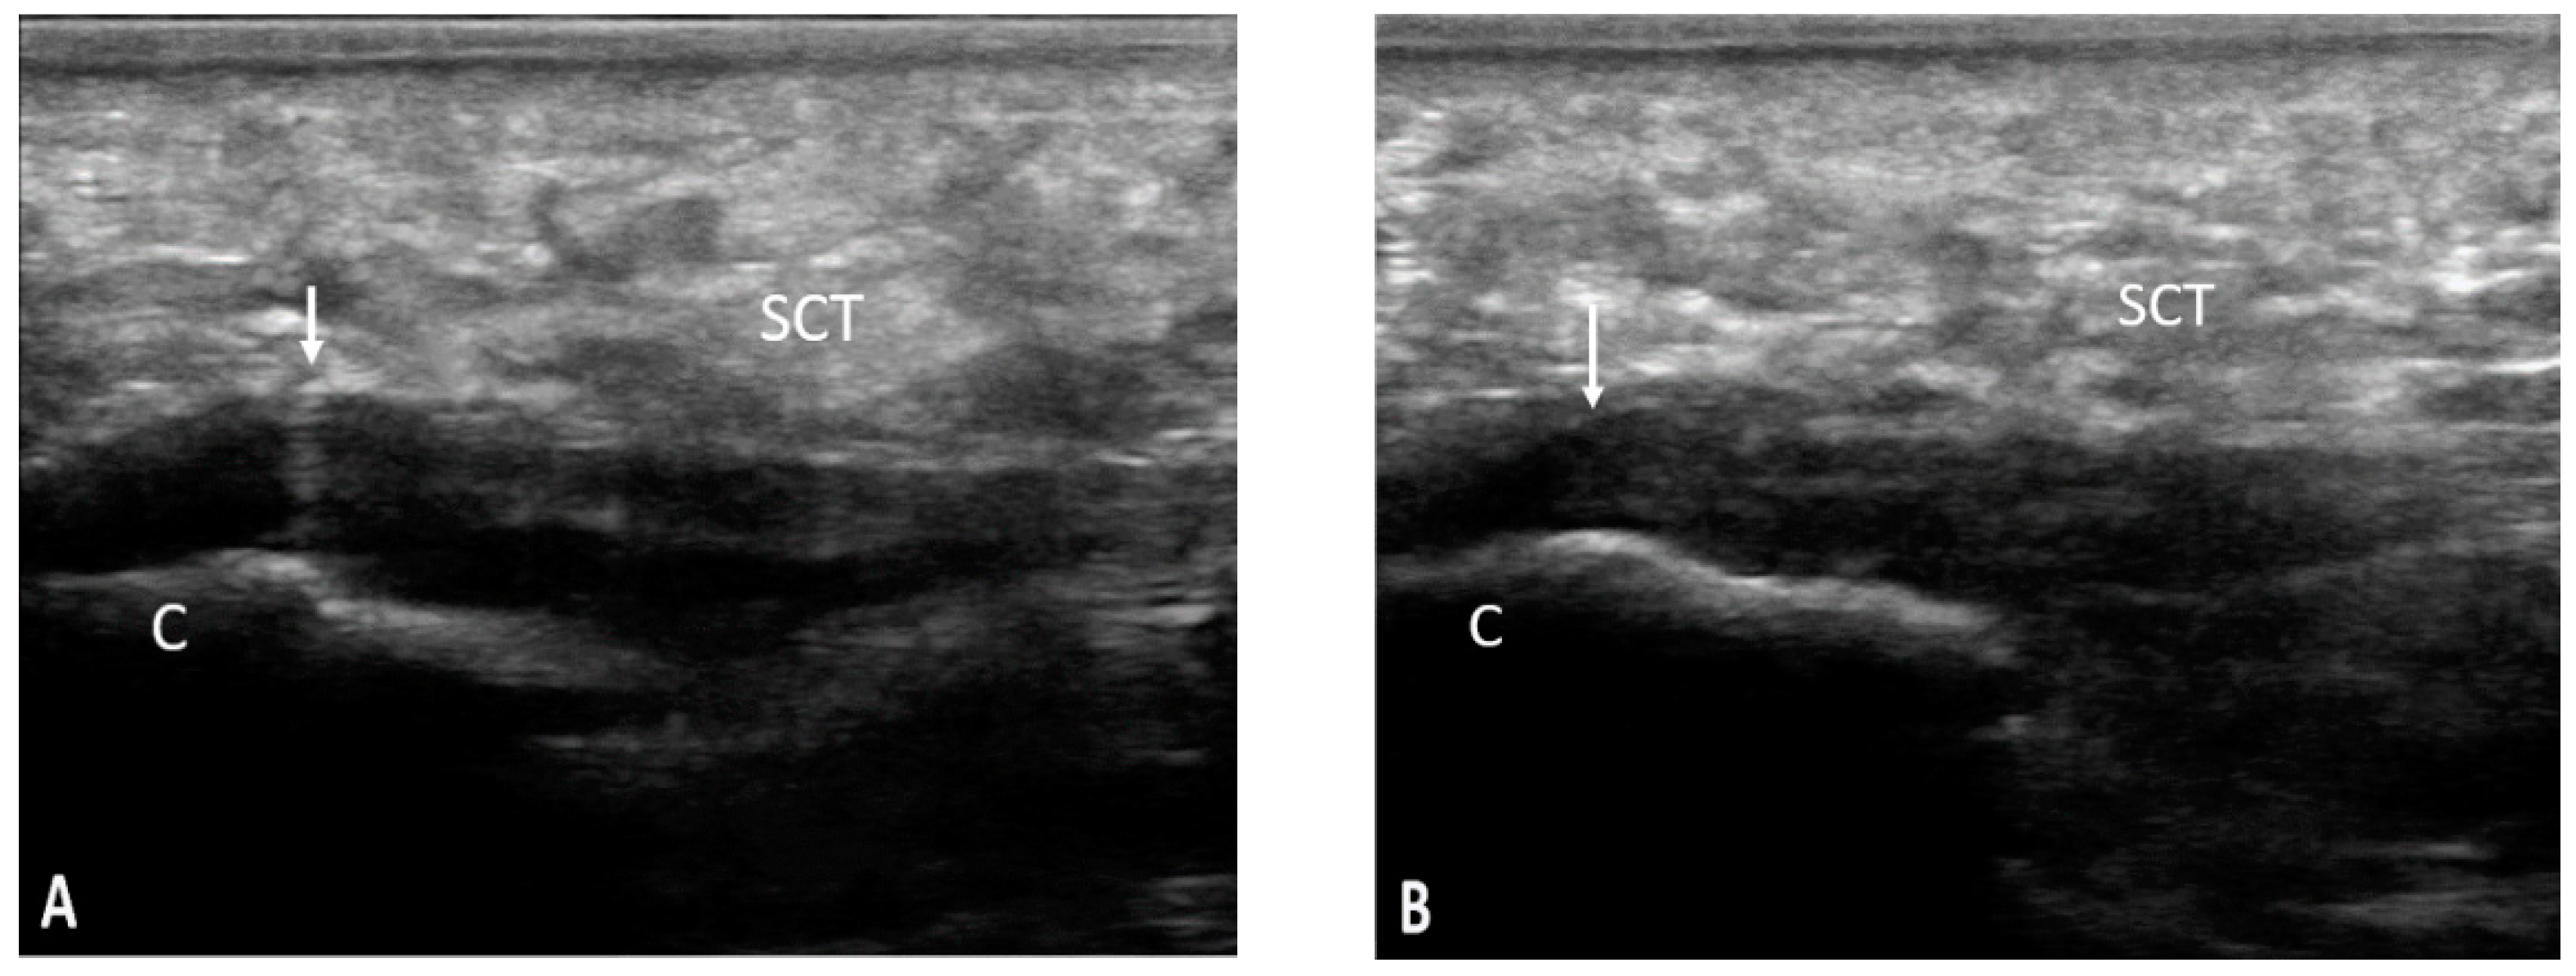

Figure 4. SCT—subcutaneous cellular tissue; C—calcaneus; ↓—plantar fascia; pathology—longitudinal scan of the plantar fascia bilaterally (A,B) showing a hypoechoic aspect, with loss of fibrillary pattern, thickening, and anterior convexity of the fascia with the presence of irregularities of the calcaneus cortex at the insertion.